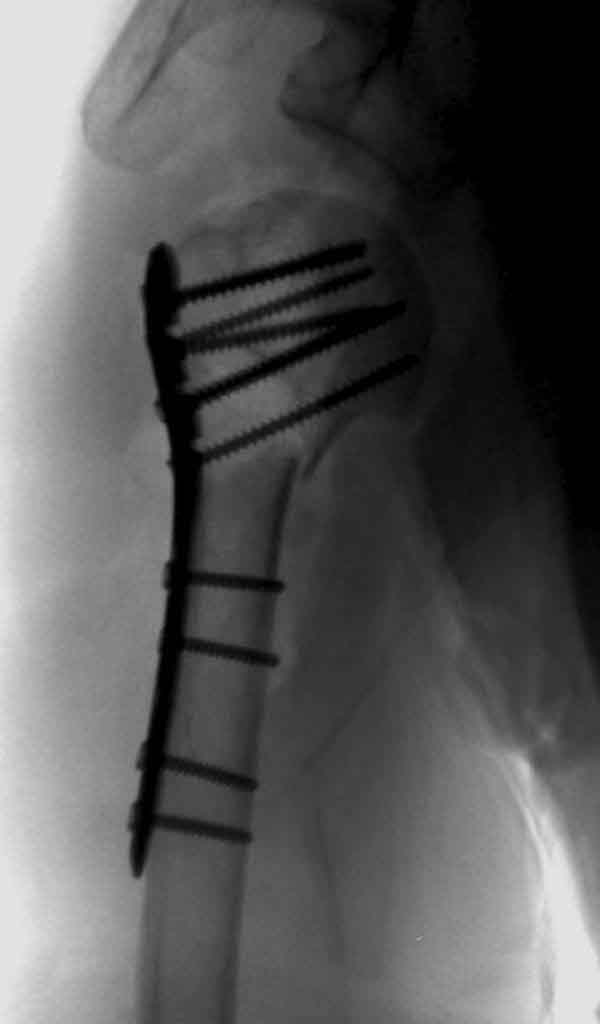

Здесь результат похожего случая, больная 87 лет, отягощенная сердечными делами и два года назад установка pacemaker и нескольких стентов. На третий день, сегодня утром сделали операцию. Послеоперационный псевдовывих связанный с релаксацией мышц и общим обезболиванием.